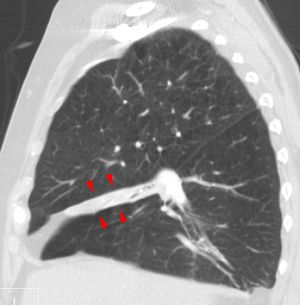

임상적으로 유의미한 무기폐는 일반적으로 흉부 엑스레이에서 관찰 가능하며, 폐의 불투명화 및/또는 폐 용적 감소와 같은 소견을 보일 수 있다. 수술 후 무기폐는 양쪽 기저부에서 나타나는 양상을 보인다. 무기폐의 원인이 임상적으로 명확하지 않은 경우 흉부 CT 또는 기관지 내시경이 필요할 수 있다.[10] 무기폐의 직접적인 징후로는 엽간 열구 및 흉강 내 이동성 구조의 변위, 영향을 받지 않은 동측 폐엽 또는 반대쪽 폐의 과도한 팽창, 그리고 허탈된 폐엽의 불투명화가 있다.[10] 흉부 엑스레이에서 임상적으로 유의미한 소견 외에도, 환자는 횡격막의 상승, 기관, 심장 및 종격동의 이동, 폐문의 변위 및 육아종의 이동과 같은 간접적인 징후와 증상을 나타낼 수 있다.[10]